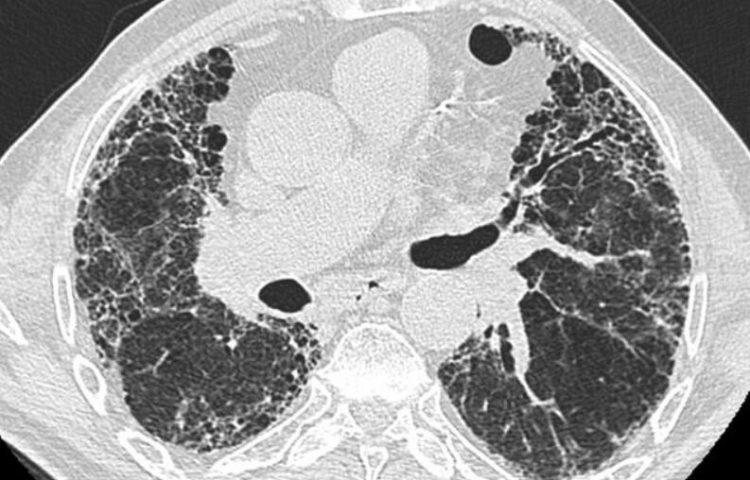

2023年10月24日,Bristol Myers Squibb(NYSE:BMY)宣布美国食品和药物管理局(FDA)已为BMS-986278授予突破性疗法认定,这是一种潜在的首创性口服药物,为进展性肺纤维化(PPF)的治疗提供新途径。进展性肺纤维化是一种具有毁灭性和威胁生命的疾病,目前只有一种治疗方法被批准用于其治疗。本文将深入探讨这一好消息,分析BMS-986278的突破性潜力以及它对肺纤维化患者的重大影响。

获得FDA的突破性疗法认定是基于全球范围内进行的随机分组的2期研究结果,该研究评估了BMS-986278治疗与安慰剂在特发性肺纤维化(IPF)和PPF患者中的安全性和疗效。在IPF队列中,允许稳定的抗纤维化药物背景治疗,而在PPF队列中则可以选择性使用免疫抑制药物。PPF队列的结果显示,采用每日60毫克两次的BMS-986278治疗26周,与安慰剂相比,呼吸功能的百分比预测强制肺活量下降速度相对减少了69%。无论是否伴随背景治疗,BMS-986278的治疗效果都相当一致,而且耐受性良好,不良事件发生率类似于安慰剂,且停药率低。这些研究结果于2023年9月在欧洲呼吸学会(ERS)2023国际大会上进行了发布。

肺纤维化患者经历肺功能的不断下降,呼吸症状的恶化以及生活质量的降低,最终可能导致呼吸衰竭和死亡。Bristol Myers Squibb的高级副总裁兼免疫学、心血管和神经科学开发部门负责人Roland Chen博士表示:“患有肺纤维化的患者面临着肺功能的不断恶化,呼吸症状的恶化以及生活质量的降低,最终可能导致呼吸衰竭和死亡。” “FDA的突破性疗法认定强调了BMS-986278作为一种创新的首创性治疗的潜力,它可能重新定义进展性肺纤维化的标准治疗。”